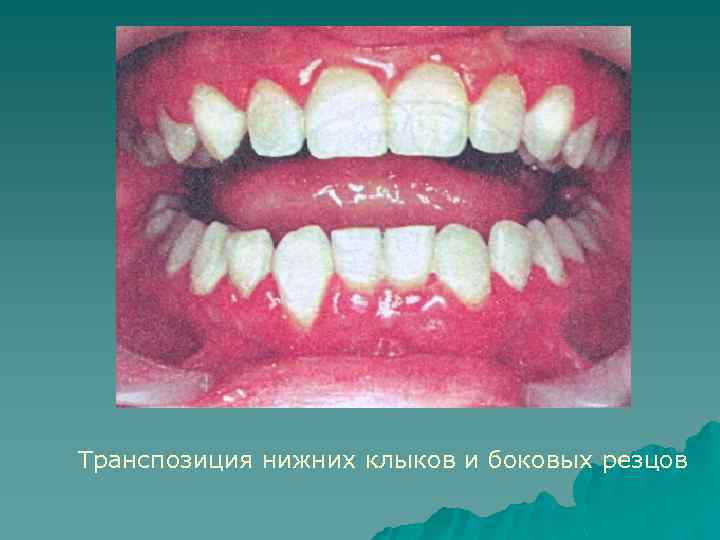

Транспозиция – взаимное изменение месторасположения зубов в зубном ряду, например клык - на месте премоляра, а премоляр - на месте клыка. Причины: атипичная закладка зачатков зубов. Близкое к транспозиции явление - взаимное смещение зачатков зубов в результате недостаточности места или в связи с провоцирующими факторами (сверхкомплектные зубы, одонтогенные новообразования и т. д. ). При этом происходит неполное изменение взаиморасположения зубов при прорезывании, выраженное в разной мере в области корней и коронок. Диагностируют при осмотре рта, а также рентгенологически

Транспозиция нижних клыков и боковых резцов